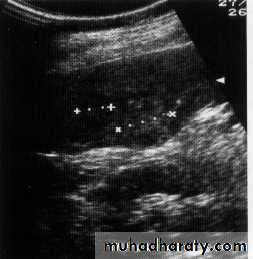

Liver cirrhosis

Cholengio ca